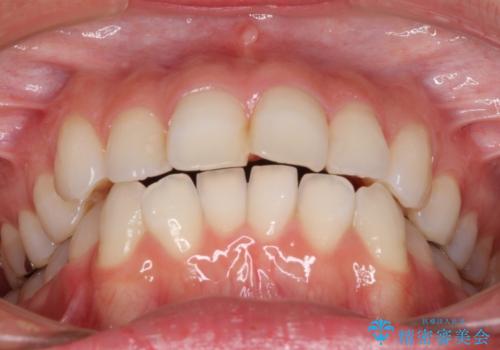

- 前歯のデコボコを気にして来院された患者様です。

主に下顎歯列全体の後方移動とIPR(歯と歯の間を削る)によってデコボコが解消するように設計し、インビザラインにより治療を行うこととしました。

舌突出癖がある方ですと、叢生が解消すると同時に前方に拡大されてしまいますが、ゴムかけをしっかりと行ってくださったこともあり、スッキリとした仕上がりとなりました。